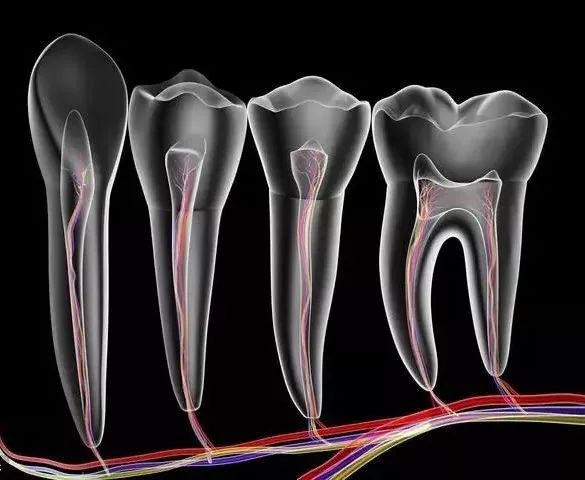

Q: 什么是根管治疗?

A: 这是目前最有效、最常见的治疗牙髓病和根尖周病的方式,可以消除牙齿内部炎症及其病变源,预防炎症加重扩散,从根本治愈。

你就需要做根管治疗了。其过程就是先将牙齿内部坏死的牙髓清理干净,再放入永久性消炎杀菌的药物,最后进行冠修复来拯救这颗牙齿。

要知道,牙齿龋坏最终会导致疼痛难忍,其实就是伤到牙神经了。当牙齿龋坏到一定程度需要做根管治疗了,那么杀神经是根管治疗必经的一步。

第一步:开髓

先在牙齿上开一个直通内里、 方便操作的大门。

第二步:杀神经

出了问题的牙神经会在牙齿内部腐坏、发酵,造成严重的感染和疼痛。所以,我们需要将牙神经杀死,然后和坏死的组织一起清理出来,来消除炎症。

第三步:填充

放入永久性消炎杀菌的药物,对根管进行严密填充,保证根管之后不会再出现炎症。

最后给牙齿做一个全瓷/烤瓷牙冠,起到保护作用,同时也解决了牙齿颜色灰暗的问题,更加美观。